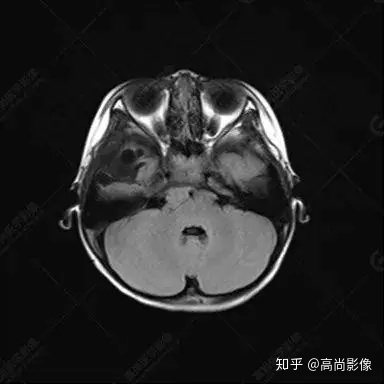

右側(cè)顳葉腫瘤切除術(shù)后(具體不詳):右側(cè)顳部骨質(zhì)不連續(xù)呈術(shù)后改變,右側(cè)顳葉術(shù)區(qū)見片狀長(zhǎng)T1長(zhǎng)T2信號(hào)影,F(xiàn)LAIR呈低信號(hào);術(shù)區(qū)后方右側(cè)顳枕葉見一巨大占位性病變影,邊界欠清,大小約6.2×5.8×4.3cm(前后×左右×上下),信號(hào)不均勻,T1WI呈等稍低信號(hào)間雜少許高信號(hào),T2WI呈高稍低混雜信號(hào),DWI示部分病灶彌散受限,相應(yīng)ADC圖減低,磁敏感序列見部分呈極低信號(hào),增強(qiáng)掃描可見明顯不均勻強(qiáng)化,鄰近硬腦膜及小腦幕增厚并明顯強(qiáng)化;另延髓右前方及右側(cè)橋小腦角區(qū)見一不規(guī)則形異常信號(hào)影,大小約3.2×1.3×3.7cm(左右×前后×上下),呈長(zhǎng)T1稍長(zhǎng)T2信號(hào),F(xiàn)LAIR呈等信號(hào),DWI未見受限,增強(qiáng)后明顯均勻強(qiáng)化,鄰近腦膜明顯強(qiáng)化。鄰近腦實(shí)質(zhì)及右側(cè)顳角明顯受壓;左側(cè)大腦半球未見局灶性信號(hào)異常,中線結(jié)構(gòu)稍左移。

右側(cè)顳葉腫瘤切除術(shù)后:現(xiàn)術(shù)區(qū)后方右側(cè)顳枕葉及延髓右前方占位,右側(cè)顳枕部硬腦膜及小腦幕明顯強(qiáng)化,結(jié)合既往影像資料,考慮為胚胎源性惡性腫瘤,如非典型畸胎樣/橫紋肌樣瘤(AT/RT)或原始神經(jīng)外胚層腫瘤(PNET)。